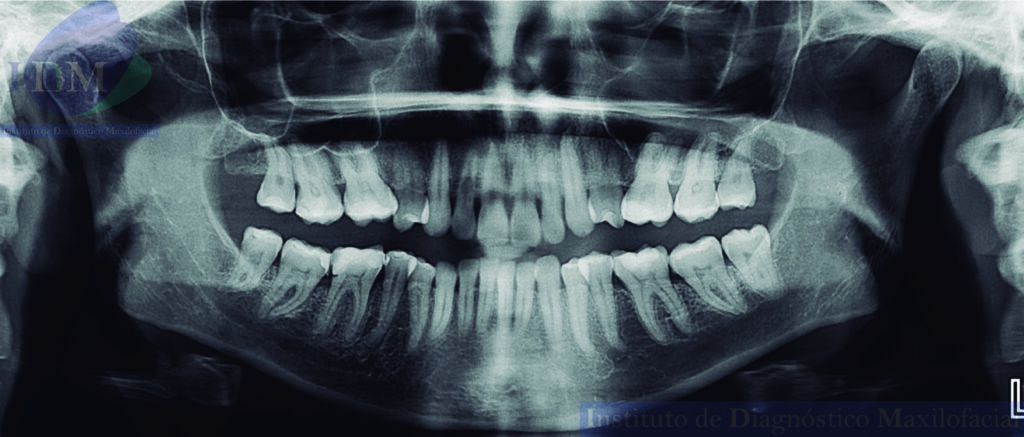

Radiografia Panorámica

En la radiografía panorámica (Figura 1), se aprecia imagen radiolúcida unilocular, proyectada a nivel de tercio apical de pieza 22 y 23, de limites definidos, bordes parcialmente corticalizados.